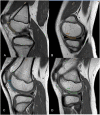

Objective: To investigate compositional changes in the distal femoral condylar cartilage (FCC) of children and young adults with and without discoid meniscus by T2 relaxation time mapping.

Design: We retrospectively reviewed knee magnetic resonance images including sagittal T2 maps of distal FCC performed in patients with or without discoid meniscus. Combined meniscal pathology such as degeneration or tears was also reviewed. Regions of interest were selected, and T2 relaxation time profiles were generated according to medial and lateral and FCC and according to weight-bearing and non-weight-bearing FCC. Nonparametric comparison tests using median values were performed.

Results: Seventy-nine knees from 73 patients (2-20 years) including 45 knees with lateral discoid meniscus (discoid group) were studied. T2 values of FCC showed negative correlation with age in both the discoid and nondiscoid groups (P < 0.01), except for medial weight-bearing FCC. In the discoid group, T2 relaxation times of lateral weight-bearing FCC (median, 46.5 ms) were lower than those of lateral non-weight-bearing (median, 53.2 ms; P < 0.001) and medial weight-bearing (median, 50.5 ms; P = 0.012) FCC. Lateral weight-bearing FCC also showed lower T2 values than other areas in patients with meniscal pathology in the discoid group. However, T2 relaxation times did not differ between the discoid and nondiscoid groups in patients without meniscal pathology.

Conclusions: Children and young adults with discoid meniscus have lower T2 relaxation times in lateral weight-bearing FCC compared with non-weight-bearing or medial FCC, suggesting compositional changes have occurred in these patients.